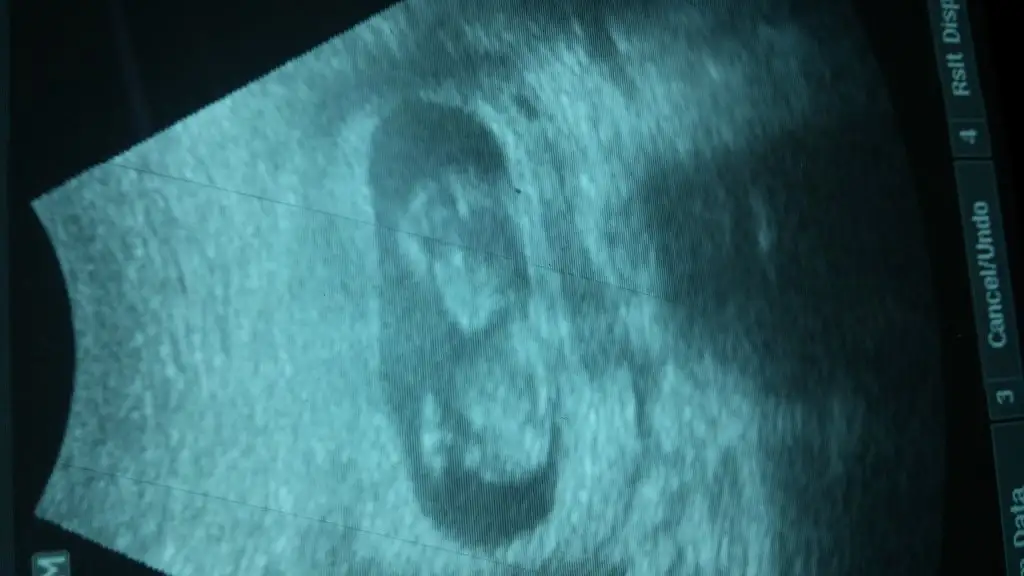

Kizlar merhaba bana da bi yorum yapabilir mi anlayanlarEki Görüntüle 1537546 Eki Görüntüle 1537545 Eki Görüntüle 1537545 Eki Görüntüle 1537546

Teşekkürler jadem :)Kız sanırsaamm

Iste o pipimi acaba yaaaa :-DGaliba erkek :S bir pipi gördüm sankiii

Teşekkürler jadem :)ben kiz hissediyorumvama bakalim artik hayirlisi ins.